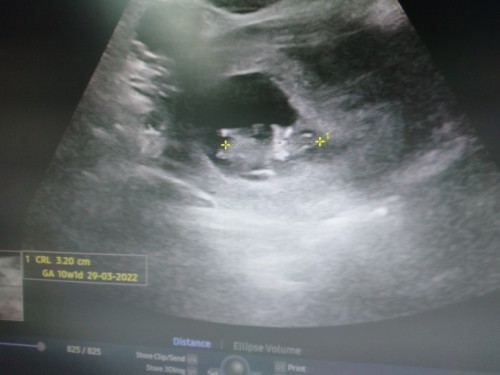

รูปนี้ซาวด์ตอน10สัปดาห์ ยังไม่รู้เพศเลยค่ะ 😅